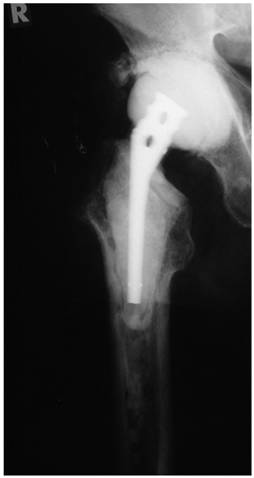

Figure 2

Articulating hip spacer in situ, the partial cementation of the spacer onto the proximal femur provides a rotational stability; at prosthesis reimplantation, the spacer can be removed at one piece, leaving no cement particles in the femoral canal.